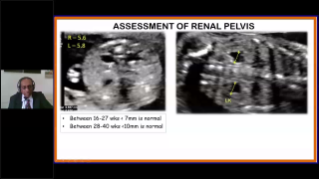

Geoptimaliseerde workflows in gynaecologie en verloskunde zijn noodzakelijk ter ondersteuning van grote pati?ntenvolumes aan screeningbezoeken voor vrouwen. Misvormingen van het centrale zenuwstelsel (CZS) zijn bijvoorbeeld een van de meest voorkomende aangeboren afwijkingen. Als gevolg van verschillende beeldvormingscondities, zoals een slechte foetale positie, is de MSP zeer moeilijk te vinden in een 2D-echografie. Daarom kunnen geautomatiseerde detectie en metingen de scaneffici?ntie sterk verbeteren.